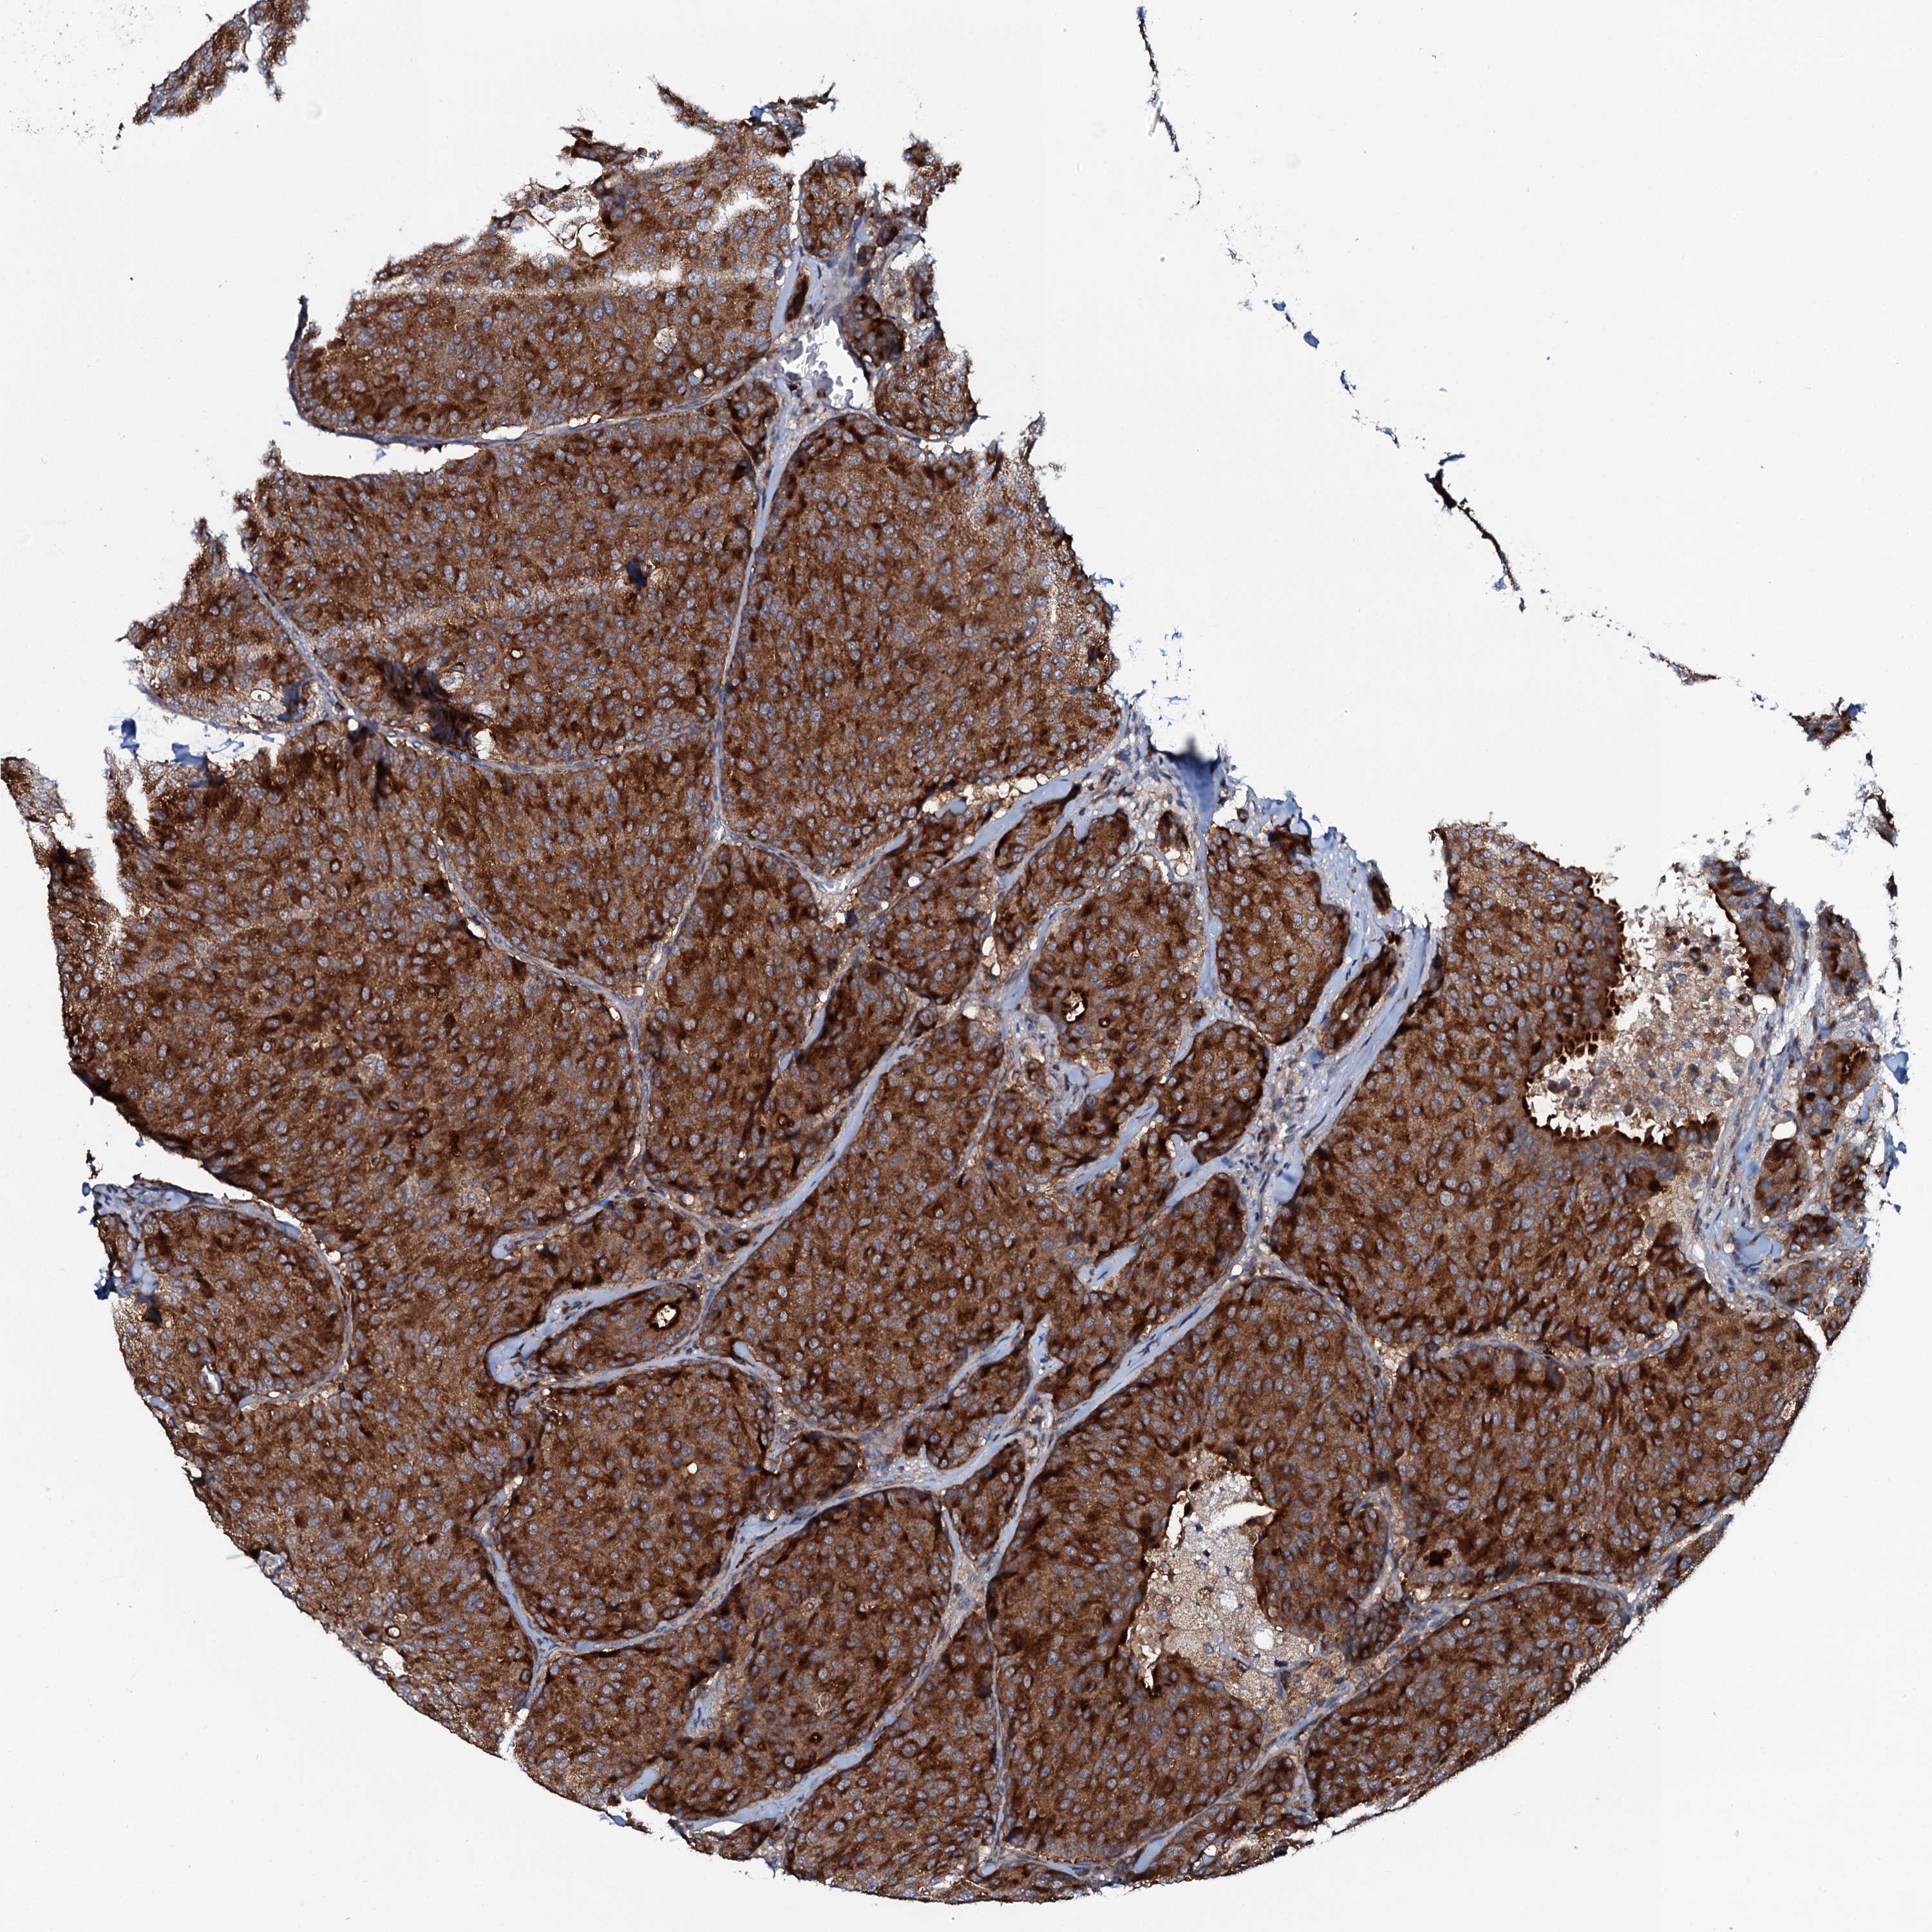

CANCER BREAST CANCER Show tissue menu

BRCA TCGA BRCA VALIDATION PROTEIN EXPRESSION